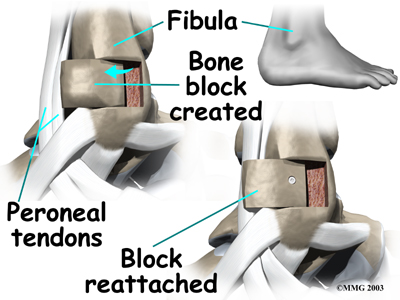

Bony Blocks

The purpose of a bony block is to form a barrier that keeps the tendons from slipping out of place. The block is usually formed with bone taken from the lower end of the fibula bone.

To create a bony block, the surgeon opens the skin along the lower edge of the fibula. The surgeon then measures a small area on the back of the fibula, near the lower tip of the bone. A special tool is used to cut this small section of the fibula. The cut only goes partway through the bone.

The surgeon slides the small block of bone backward, out of its original spot. The bone may be rotated slightly to create a solid barrier that will help keep the tendons from sliding around the lower edge of the fibula. A screw is inserted through the small block of bone into the fibula. The screw keeps the bony block in its until it heals.

The surgeon checks the fit to make sure the tendons can glide behind the new block of bone without slipping out of place. The skin is then closed and sutured.